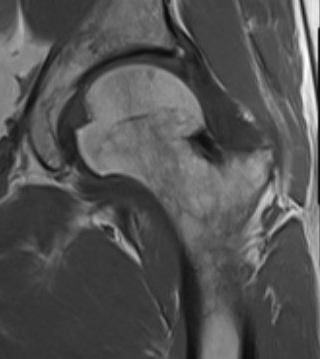

Osteopoikilosis

Rare inherited benign condition characterised by multiple bone islands

AD inheritance, high penetrance

Lesions clustered around joints

- typically arms, legs and pelvis